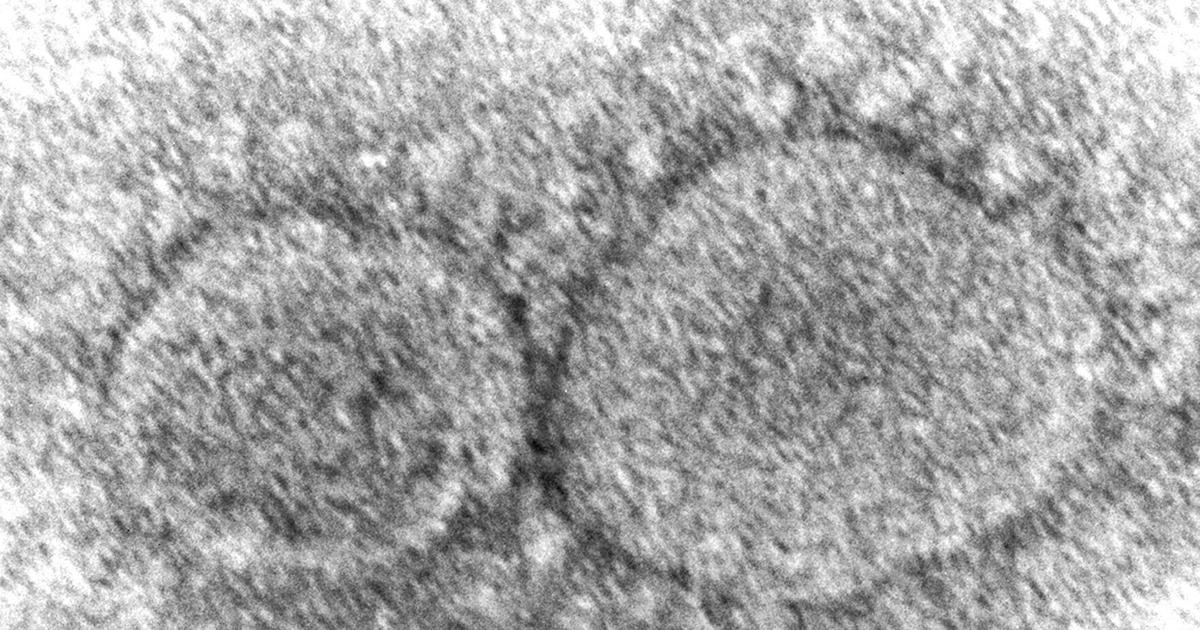

Omicron subvariant BA.5 is proving more evasive to existing immunity and more transmissible than anything seen with omicron previously, April Holland, Public Health deputy director, told the Board of Commissioners at its most recent meeting.